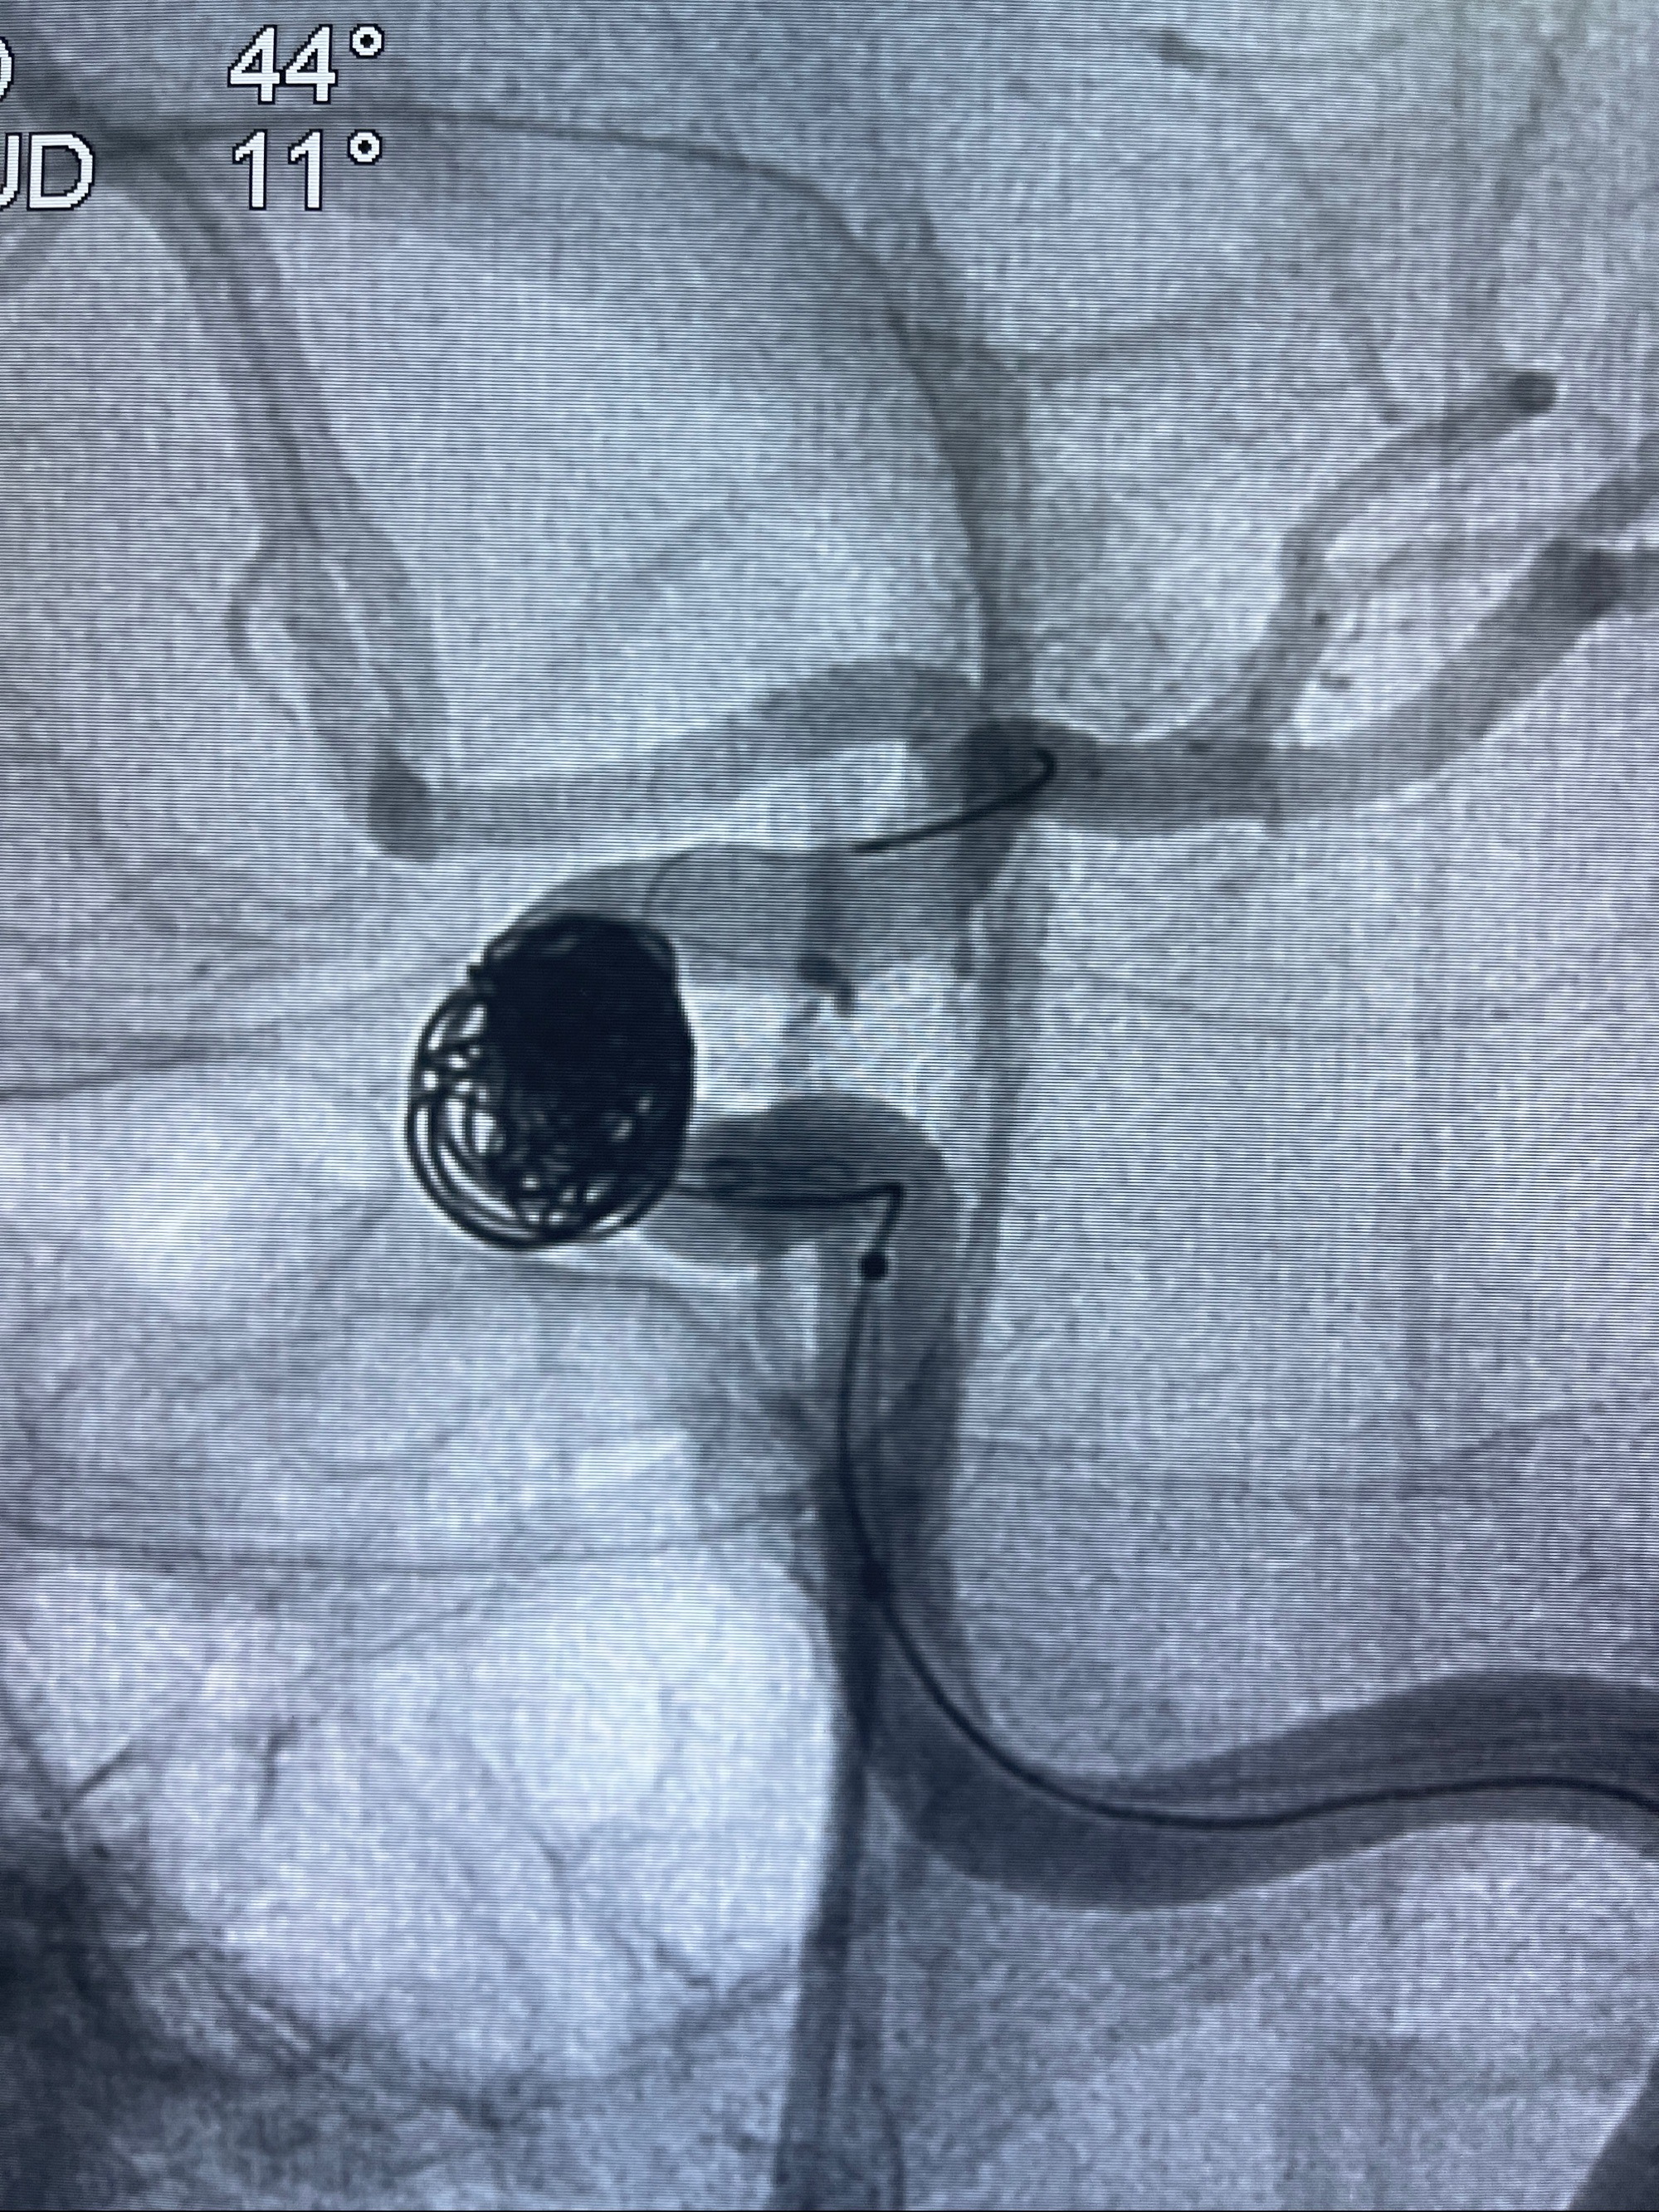

- Tubridge 4.0-20mm密网支架

- 加奇微弹簧圈:7*30/6*20/5*20/2*8

术后3D显示支架贴壁佳